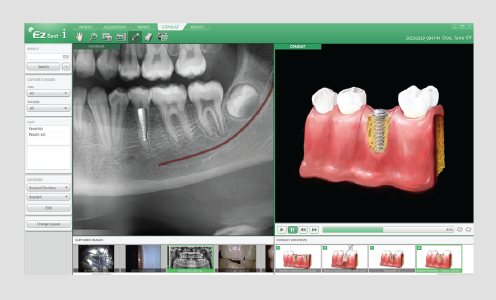

CLIC IMPLANTE DE SIMULACIÓN

El nuevo proceso racionalizado mejora la facilidad de uso y eficiencia de la planificación de implantes.

ARRASTRAR Y SOLTAR

Varios diseños ya hechos y un método para arrastrar y soltar permiten crear cualquier tipo de combinación de imagen de manera sencilla. Puede compartir el informe y las imágenes por mail, PDF, CD y DICOM.